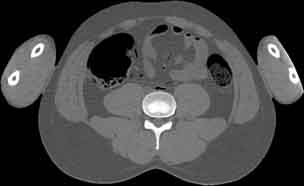

Visible Human male: Sectio transversalis 1719

CT

NMR

Pd                          / T2 \                         T1